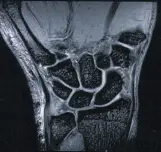

МРТ диагностика суставов, что дает расширенные возможности в установлении диагноза и в выборе тактики лечения.

МРТ лучезапястного сустава